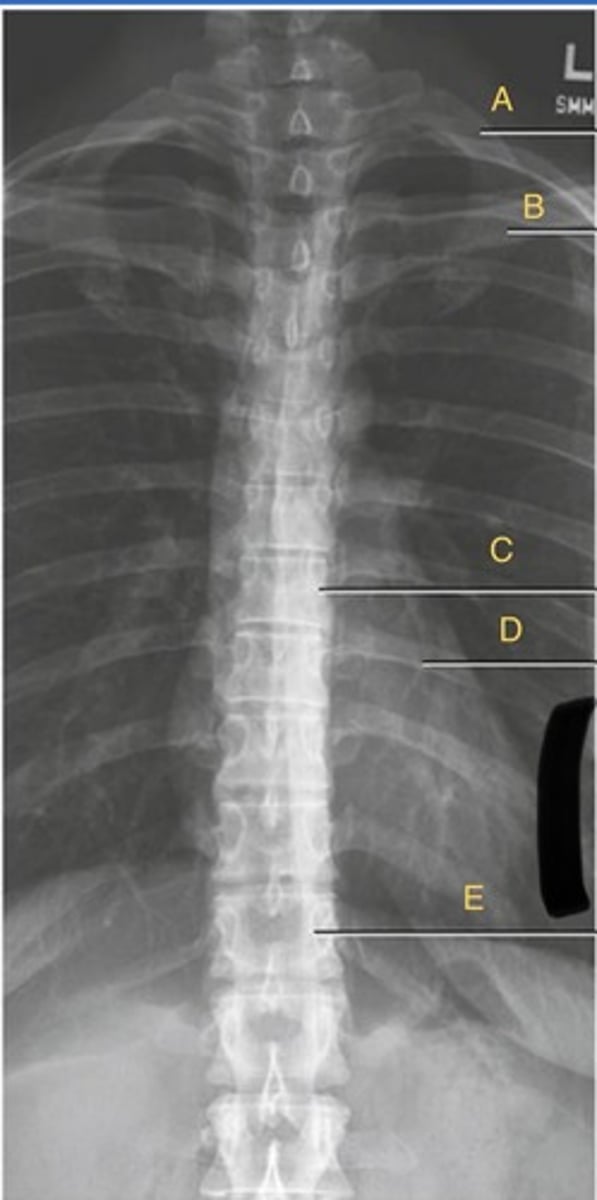

L 1st posterior rib

A.

L 10th posterior rib

B.

T11 spinous process

C.

T12 body

D.

T8-9 intervertebral disk space

E.

T7 body

F.

T1 body

G.

AP t-spine

What position?